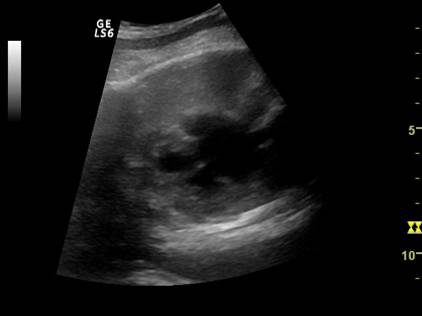

Fig. nr. 263.

Lichid pericardic (SAGEATA) , fat cu anamnios si retard major de

crestere

intrauterina RCIU,cu suspiciunea de sindrom genetic